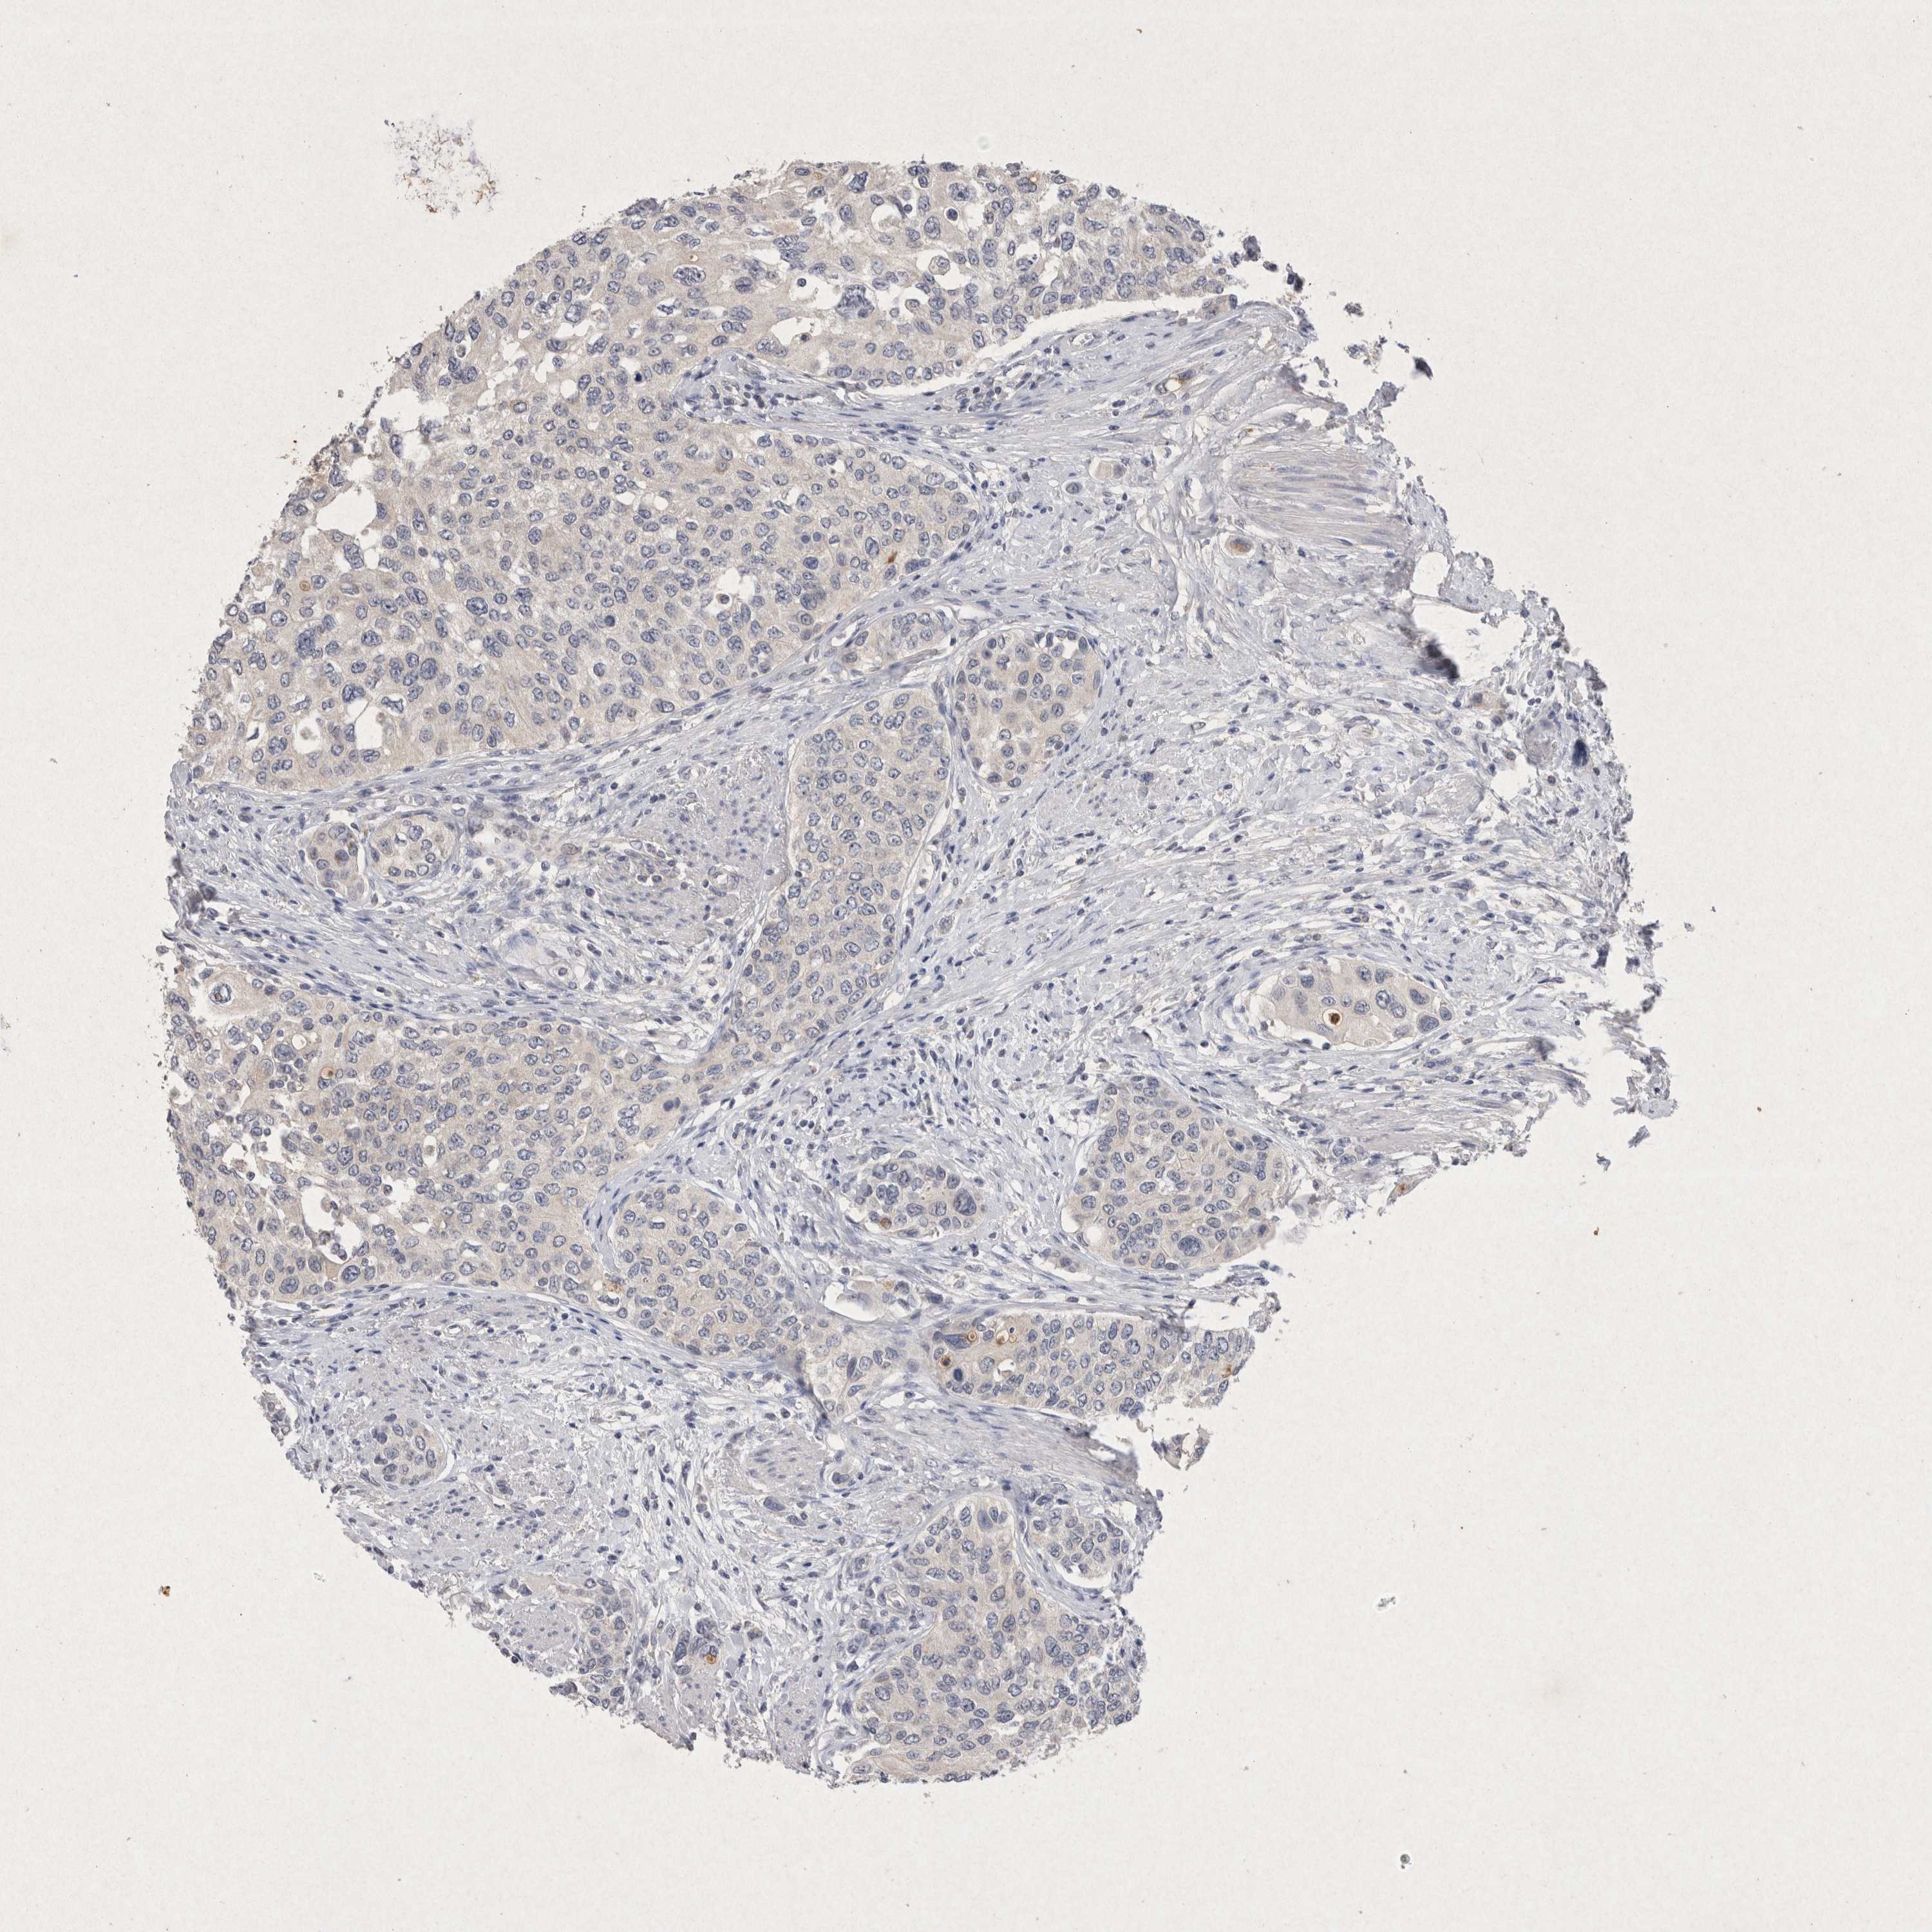

UROTHELIAL CANCER - Protein expressioni

A mouse-over function shows sample information and annotation data. Click on an image to view it in a full screen mode. Samples can be filtered based on level of antibody staining by selecting one or several of the following categories: high, medium, low and not detected. The assay and annotation is described here.

Note that samples used for immunohistochemistry by the Human Protein Atlas do not correspond to samples in the TCGA dataset.

Antibody stainingi

Antibody staining in the annotated cell types in the current human tissue is reported as not detected, low, medium, or high, based on conventional immunohistochemistry profiling in selected tissues. This score is based on the combination of the staining intensity and fraction of stained cells.

Each image is clickable and will lead to virtual microscopy that enables deeper exploration of all samples and also displays staining intensity scores, fraction scores and subcellular localization as well as patient and tissue information for each sample.

Antibody HPA038469

Antibody CAB022664

Antibody CAB034035

Staining

High

Medium

Low

Not detected

Intensity

Strong

Moderate

Weak

Negative

Quantity

>75%

75%-25%

<25%

None

Location

Nuclear

Cytoplasmic/membranous

Cytoplasmic/membranous,nuclear

Urothelial carcinoma, High grade

Urothelial carcinoma, Low grade